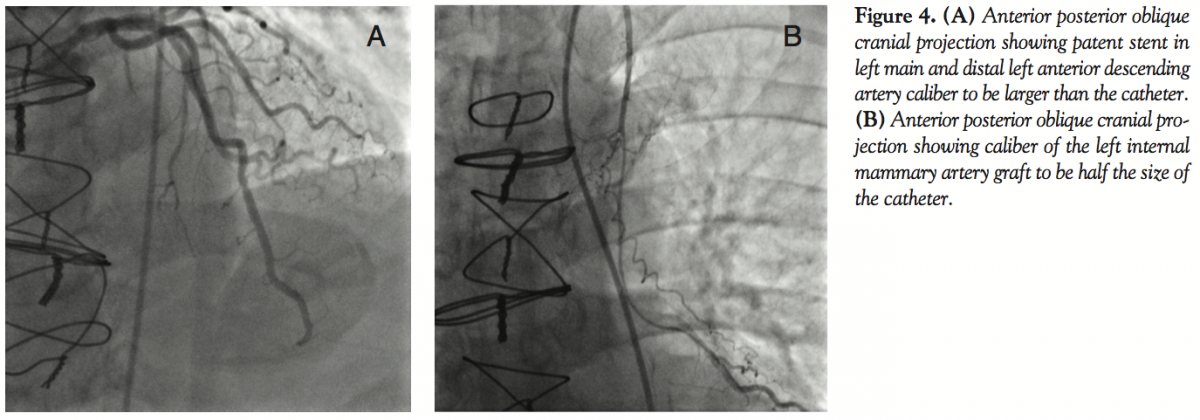

LIMA graft to be patent (Figure 2A). The ostial stenosis in the LMCA had progressed to 90% (Figure 2B) with no other new findings (Figure 2C). Because of worsening symptoms, increase in the LMCA stenosis and pressure dampening with catheter, fractional flow reserve (FFR) was performed to determine the physiologic significance of this lesion. With the pressure transducer in the obtuse marginal (OM) artery (Figure 3A), FFR using intravenous adenosine was 0.80 (Figure 3B). A bare-metal stent was implanted in the LMCA (Figure 3C). Postintervention FFR was 0.97 (Figure 3D). At 4-week follow-up, the patient was asymptomatic. The patient presented with atypical chest pain 3 months after PCI. Angiography showed a patent LMCA stent (Figure 4A) with significant atresia of the entire length of the LIMA graft (Figure 4B). He was maintained on aggressive medical management. Nuclear stress test done 6 months later showed no evidence of ischemia (Figure 5).

Compared with SVG, LIMA flow immediately after surgery is low and increases by approximately 30% over the next 3 months, and reaches comparable levels as SVG at about 10 months.3 The putative mechanism has been postulated to be endothelium-dependent vascular remodeling.3 If this were true, it is reasonable to speculate that any factor that interferes with the adaptability mechanism of the LIMA graft during its “maturation” phase, such as increase in blood flow through the native coronary artery because of intervention performed, as in our case, may affect its flow and consequently, its caliber. In our case, the first reported case in man that demonstrates atresia after full LIMA graft maturation, the stimulus for growth was diminished, as was the size of the vessel. We postulate that were LAD flow to decrease again as a result of a new lesion, the LIMA graft would have a further stimulus for growth and its size would enlarge.

In conclusion, this case illustrates the effect of increasing antegrade flow down the LAD, and suggests that the amount of flow is important in the size of the IMA graft.